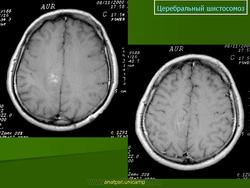

Шистосомоз